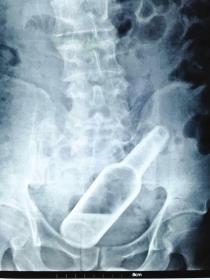

“因为物体边缘比较光滑,手术的时候,我们两个人合作,一个人顺着肚子一点点推,推到肛门口,我把异物拿了出来,大概花了十分钟时间。”郁峰说,这名男子运气算好的,因为根据拍片检查,当时那根振动棒已经挤到了肚脐的部位,情况其实已经相当危险。医生提醒“那根振动棒有20公分,人的直肠只有18公分,它的长度已经超过直肠了,到达乙状结肠,会引起肠子破裂坏死,如果破了就会有生命危险。”

男子为寻刺激将20厘米塑料棒塞入肛门险致命